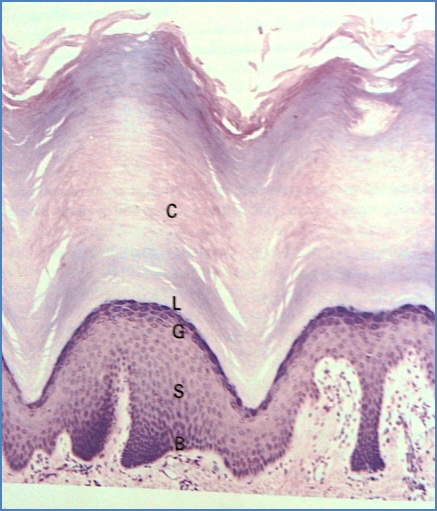

Epidermis

- Stratified squamous keratinised epithelium

- Avascular and primarily cellular (~95% keratinocytes)

- Protective, renewable barrier (0.1–1 mm thick)

Layers (from deep to superficial):

- 1. Stratum Basale (Germinativum):

- Single layer of cuboidal/columnar cells

- Stem cells divide and differentiate into keratinocytes over ~14 days

- Attached to basement membrane via hemidesmosomes

- 2. Stratum Spinosum (Prickle cell layer):

- Several layers of polyhedral keratinocytes

- Tonofibrils attach to desmosomes

- Contains Langerhans cells (APCs)

- Lamellar bodies → extracellular lipid barrier

- 3. Stratum Granulosum:

- 3–5 layers of flattened keratinocytes

- Loss of nuclei

- Keratohyalin granules (profilaggrin, keratin, loricrin)

- Lamellar bodies secrete lipid-rich “mortar” between cells

- 4. Stratum Lucidum:

- Only in thick, glabrous skin (palms/soles)

- Flattened, anucleate cells

- 5. Stratum Corneum:

- 5–50 layers of dead, flattened squames

- No nuclei or organelles

- Keratin and lipids create a strong moisture-retaining barrier

- Thickest in glabrous skin